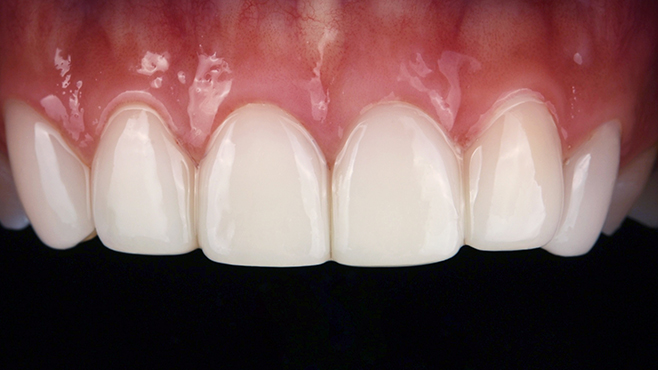

before

after

※ 위 임상사진은 동일조건으로 촬영되었으며, 사진에 대한 별도의 조작이 처리되지 않았습니다.

※ 위 임상사진 및 포트레이트는 환자와의 포괄적인 초상권 계약 이후 사용하고 있습니다.

※ 수술 및 치료과정에서 부작용이 발생할 수 있으므로 충분한 상담과 신중한 판단이 요구됩니다.

실제 치료 사례

수많은 환자들이 고민 끝에 선택한 치료,

그리고 그 후의 놀라운 변화

- ※ 위 임상사진은 365서울원탑치과에서 진료를 시작하고 마친 동일한 환자의 사진입니다.

- ※ 위 임상사진은 동일한 장소에서 동일한 조건으로 촬영되었으며, 사진에 대한 별도의 조작이 처리되지 않았습니다.

- ※ 수술 및 치료 과정에서 부작용이 발생할 수 있으므로 의료진과의 충분한 상담과 신중한 판단이 요구됩니다.